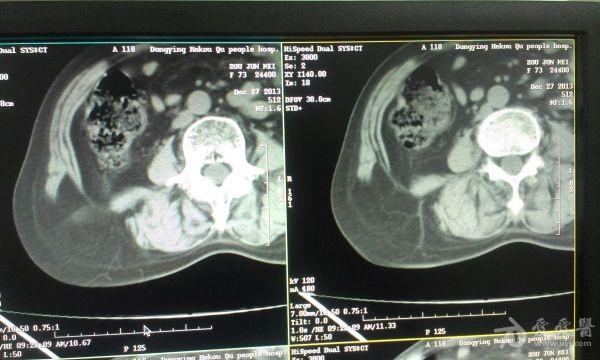

挺经典的腰疝

右腰部包块,随呼吸可运动。

非常经典的ct片,不知是继发于何种原因还是先天性的?里面内容物一般是肠管,很少发生较窄、嵌顿。